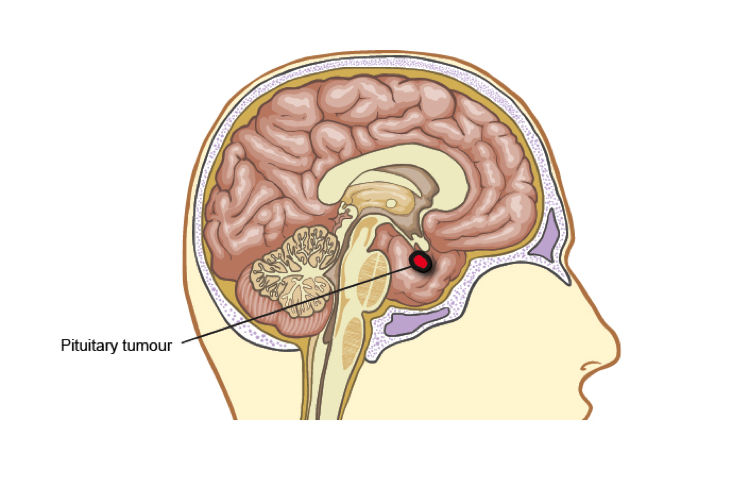

Το αδένωμα υπόφυσης είναι ένας συνήθως καλοήθης όγκος που αναπτύσσεται από τα κύτταρα της υπόφυσης, ενός μικρού αλλά ιδιαίτερα σημαντικού ενδοκρινικού αδένα στη βάση του εγκεφάλου. Ανάλογα με το μέγεθός του, διακρίνεται σε μικροαδένωμα (διάμετρος μικρότερη από 10 χιλιοστά) και μακροαδένωμα (διάμετρος μεγαλύτερη από 10 χιλιοστά). Παράλληλα, ταξινομείται σε εκκριτικό, όταν παράγει αυξημένες ποσότητες συγκεκριμένων ορμονών, και μη εκκριτικό, όταν δεν προκαλεί ορμονική υπερέκκριση. Ο τύπος και το μέγεθος του αδενώματος καθορίζουν την κλινική εικόνα, τα συμπτώματα και τη θεραπευτική προσέγγιση η οποία θα επιλεγεί για κάθε ασθενή.

Τα μη εκκριτικά αδενώματα στην αρχή δεν προκαλούν συμπτώματα, αλλά αυξάνονται προοδευτικά σε μέγεθος. Όταν το αδένωμα φτάσει περίπου τα 10 χιλιοστά σε διάμετρο (μακροαδένωμα), αρχίζει να πιέζει τους γύρω ιστούς. Αρχικά μπορεί να συμπιέσει τη φυσιολογική υπόφυση, οδηγώντας σε υποφυσιακή ανεπάρκεια, ενώ σε επόμενο στάδιο πιέζει τα οπτικά νεύρα, προκαλώντας διαταραχές της όρασης, όπως μείωση των οπτικών πεδίων.